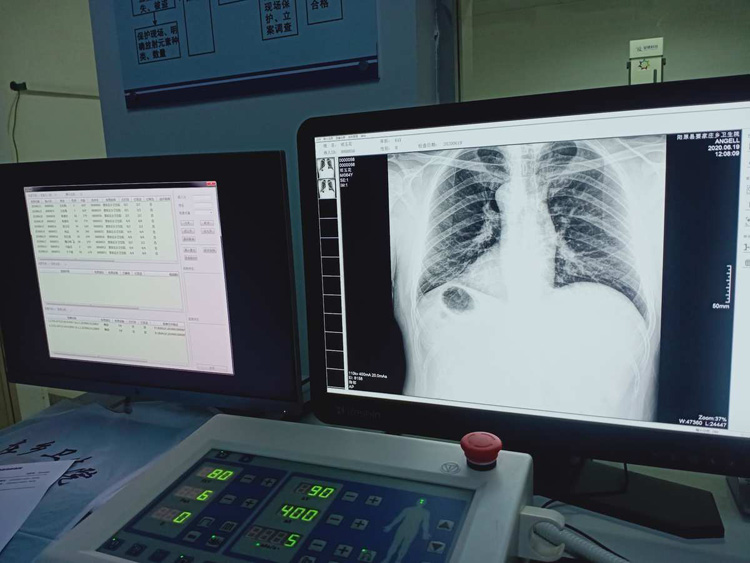

平床DR的平板探測器可以拍攝到高清的數字圖像。可以檢查身體的某個部位。頭部、胸部、腹部、上肢、下肢、正位、側位、都可以正常的拍攝。很小的劑量就可以采集到高清的檢查圖像。平板的穩定性也非常的強。DR的平板探測器跟圖像結合。噪音低、圖像的畫質呈現豐富。圖像的信息量會跟多提供給醫生參考。幫助醫生提高診斷的準確性。Digital Radiography就是數字化拍攝。平板探測器特性會對拍攝片的圖片質量有關系。

平床DR的數字影像高分辨率,動態范圍比較大,密度密度分辨率高可以看到更多細節。拍攝的速度快偽影小。比X光的的靈敏度高很多。輻射小的能量就可以拍到清晰的圖像。輻射量少30%以上。特別是對骨頭軟組織的效果更優。對結節的有沒病變的檢測查出率更高。